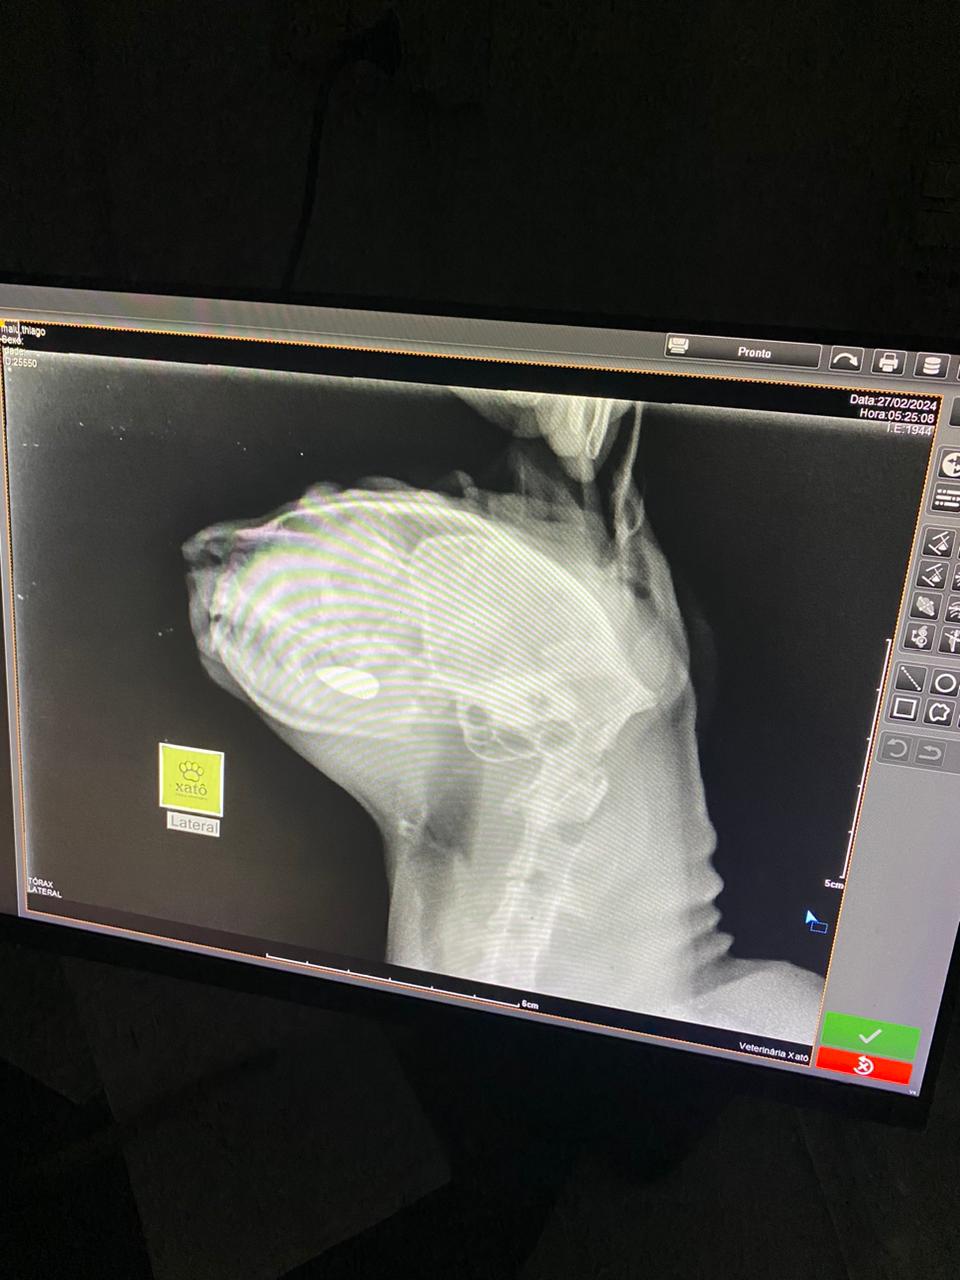

Projétil atingiu a boca do animal, que engoliu e agora está alojada em seu intestino

Mesmo com a operação em andamento, a tutora levou a gata para uma clínica de emergência veterinária e ao ser atendida, foi constado que a bala atravessou a língua da pet.

Após os primeiros atendimentos, Malu engoliu o projétil, que se alojou em seu intestino.

Malu passa bem, e segue em observação para possível cirurgia.